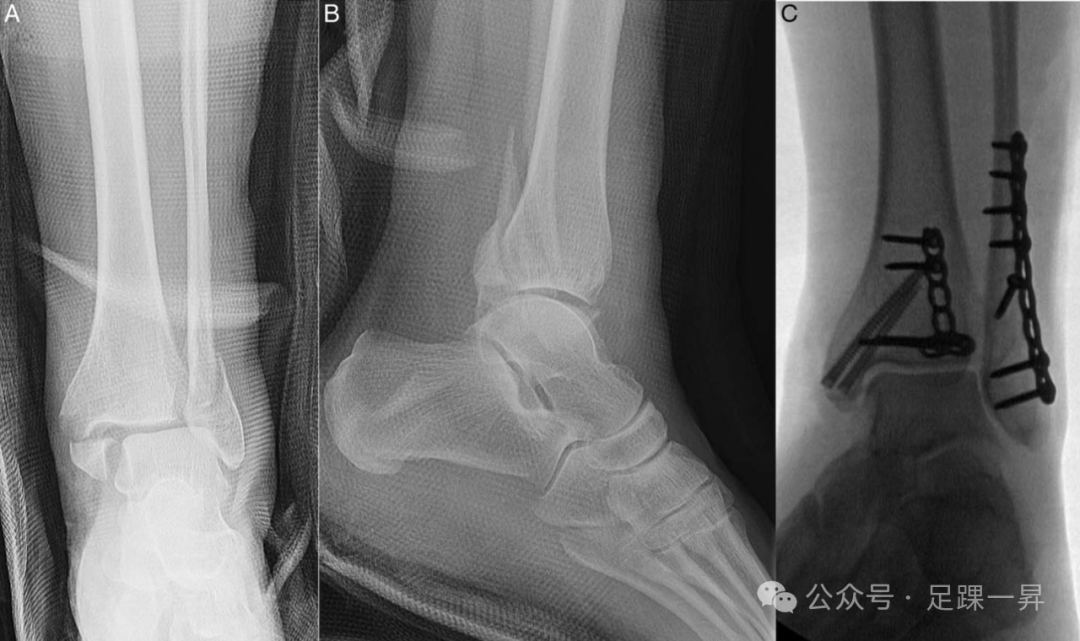

图5. 一例未使用下胫腓联合固定螺钉治疗的旋转性踝关节骨折伴踝穴增宽病例。术前非负重正位(A)和侧位(B)X线片显示三踝骨折伴踝穴增宽。(C)术中在解剖复位外踝、内踝和后踝后,通过外旋试验评估下胫腓联合稳定性,结果显示踝穴稳定。术后正位(D)和侧位(E)踝关节X线片显示踝穴维持良好,无增宽。